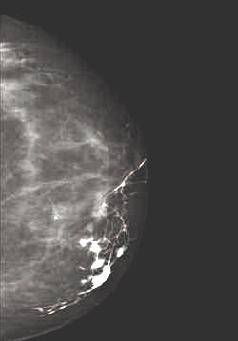

Le sein est un organe constitué de tissus mous. Il comporte des éléments hydriques (peau en surface, tissus glandulaires et conjonctifs en profondeur), des éléments graisseux (qui sont à l'origine du contraste radiologique) et des calcifications (dépôts calciques dans la fibrose, la nécrose, les parois vasculaires, la concentration de sécrétions glandulaires.) Les éléments hydriques et graisseux n’ont pas une grande différence d’atténuation, aussi les différences de contrastes sont faibles, or en mammographie, l’utilisation de produits de contraste reste limité à quelques cas très particuliers (exploration d’un canal galactophore par injection dans ce canal d’un produit à base d’iode, Figure 4). Pour obtenir un contraste suffisant, il est donc nécessaire que les rayons X ne soient pas trop perforants, c'est-à-dire utiliser un faible kilovoltage (typiquement entre 25 et 30 kV, contre souvent plus de 100 pour d’autres types de radiographie). L’information d’une mammographie est donc essentiellement contenue dans les nuances de gris (Figure 5), et il est essentiel que le film ne soit pas sur ou sous-exposé. Une bonne mammographie repose sur des choix judicieux (matériel, film, développement, etc…) et surtout sur l’expérience du radiologue. Une des difficultés de la lecture d’une mammographie provient du fait qu’un sein n’est pratiquement jamais dépourvu de diverses marques du passé (fibroses, kystes, opacités diverses) qui peuvent compliquer l’interprétation, quand ce n’est pas masquer un élément pathologique puisque les différents éléments se superposent sur le cliché. D’où, entre autre, l’intérêt de réaliser plusieurs clichés sous différents angles, et de comparer l’image radiologique des deux seins.

Le cancer du sein est le plus fréquent des cancers féminins, représentant 36 % de tous les cancers. Il est responsable de 19 % des décès féminins par cancer. Or la détection d’une tumeur de moins de un centimètre (indécelable à la palpation mais à la portée d’une mammographie) conduit le plus généralement à une guérison. C’est pourquoi les femmes de 50 à 74 ans (âge de plus grande survenue de la maladie) sont invitées à faire une mammographie (prise en charge intégralement) tous les 3 ans. Actuellement un peu plus de 40 % des femmes concernées suivent cette recommandation, ce qui reste insuffisant, même si ce taux augmente continuellement. En effet, on estime qu’une participation de 70 % des femmes à ce dépistage de masse augmenterait le taux de guérison de 30 %. En terme radiographique, un cancer est essentiellement détecté du fait de la présence de microcalcifications au niveau de la tumeur. Cependant, toute calcification n’est pas le signe d’une tumeur. En effet, on trouve des calcifications artérielles, des calcifications sous-cutanées, ainsi que des kystes de petite taille contenant du lait calcique. Il faut donc repérer les calcifications qui signalent la présence d’une tumeur. Pour cela, il existe une nomenclature qui permet l’évaluation du risque, essentiellement basée sur la taille, le nombre et la distribution des calcifications. Ainsi, les calcifications d’une taille supérieure au millimètre, de même qu’une microcalcification (inférieure au millimètre) isolée ne signalent pas un cancer. En fonction du nombre des calcifications, de leur aspect individuel, de l’aspect de l’amas, on peut donc évaluer la probabilité qu’il y ait une tumeur cancéreuse. A partir de ce moment, des examens complémentaires seront prescrits si nécessaire, en premier lieu desquels figure la biopsie qui permet l’analyste histologique des tissus suspects pour préciser le diagnostique.